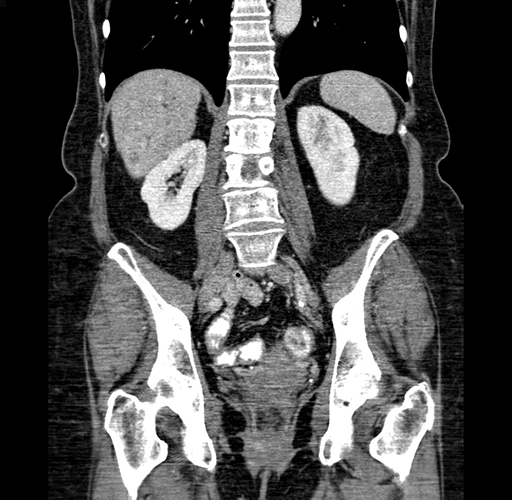

Pre-Chemo: Coronal Venous

Coronal Venous